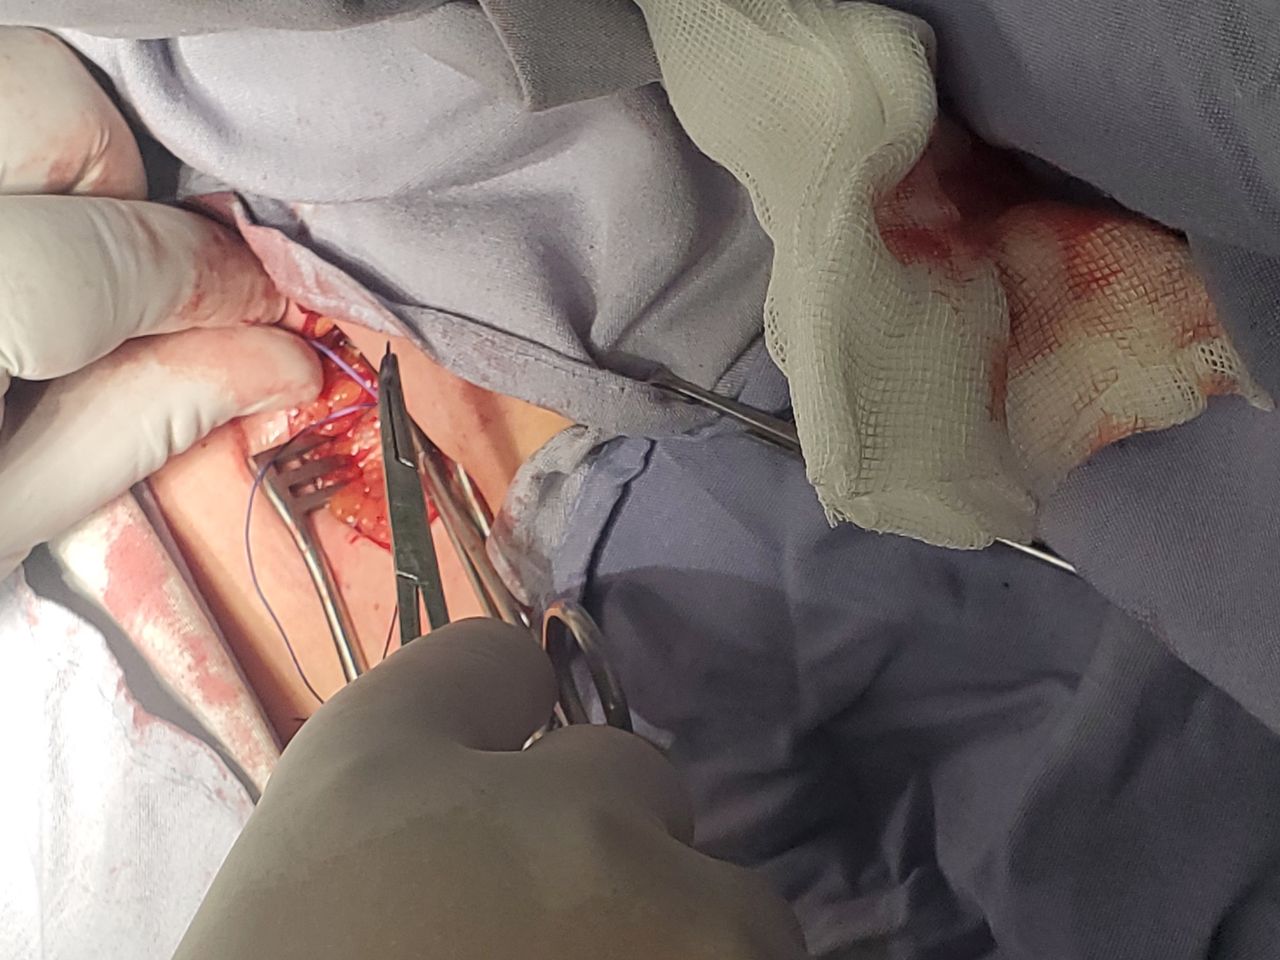

• Cateterismo cardíaco terapéutico y diagnóstico

• Colocación marcapasos endovenoso definitivo